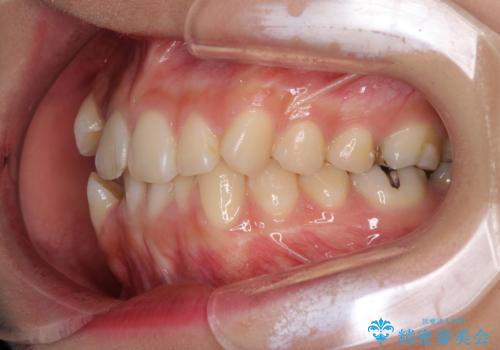

- 上下の八重歯を気にして来院された患者様です。

上下ともに八重歯の後ろの歯を1歯ずつ抜歯し、補助装置(リンガルアーチ)を用いて八重歯の位置を改善し、その後インビザラインにより矯正治療を行うこととしました。

途中海外留学をされたため、治療期間は長くなりましたが、事前に補助装置やワイヤー装置を併用したことで、きれいな歯列に仕上げることができました。